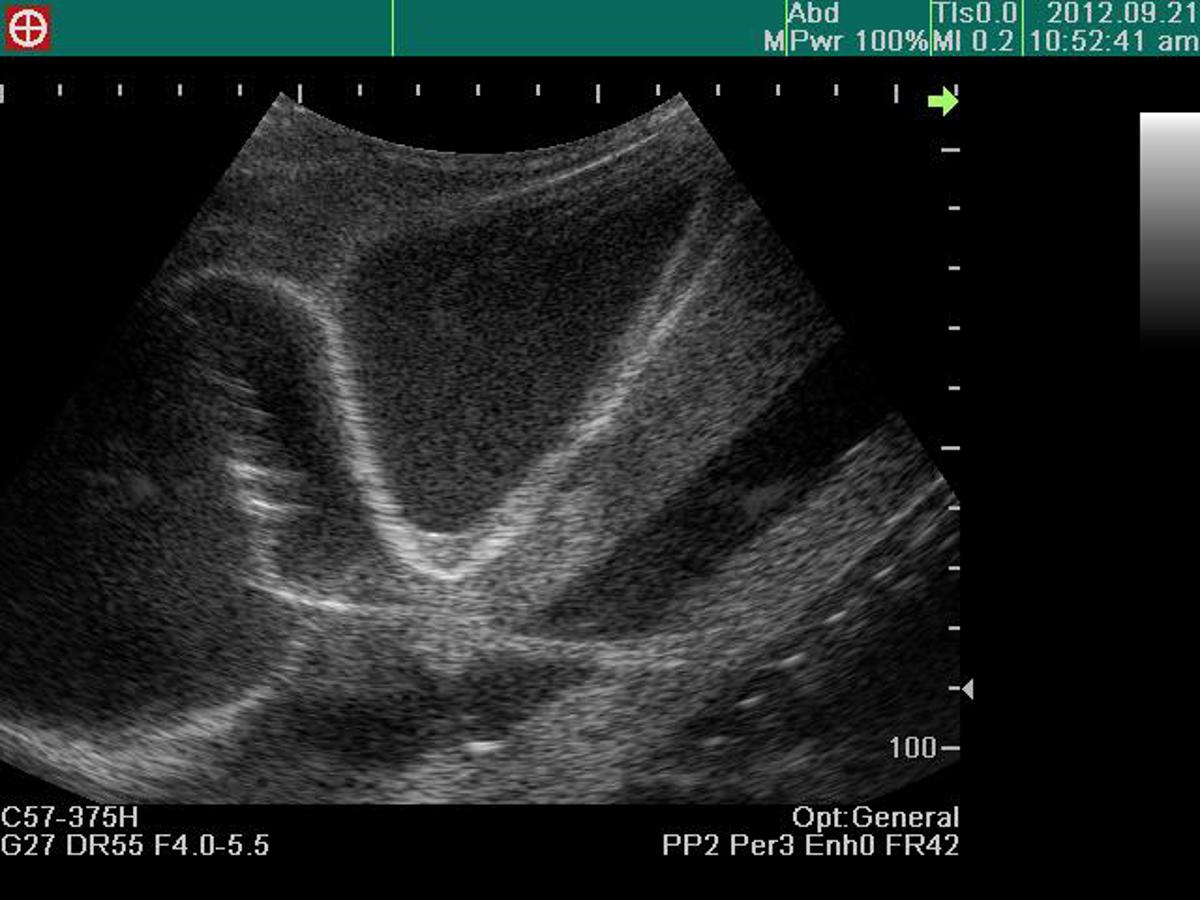

Excellent ultrasound image

Confirmation of ventricles, ribs, pericardium, liver and main artery under ultrasound scanning

Visualization of pericardial fluid using ultrasound scanning

Recognition of anatomical landmarks using ultrasound